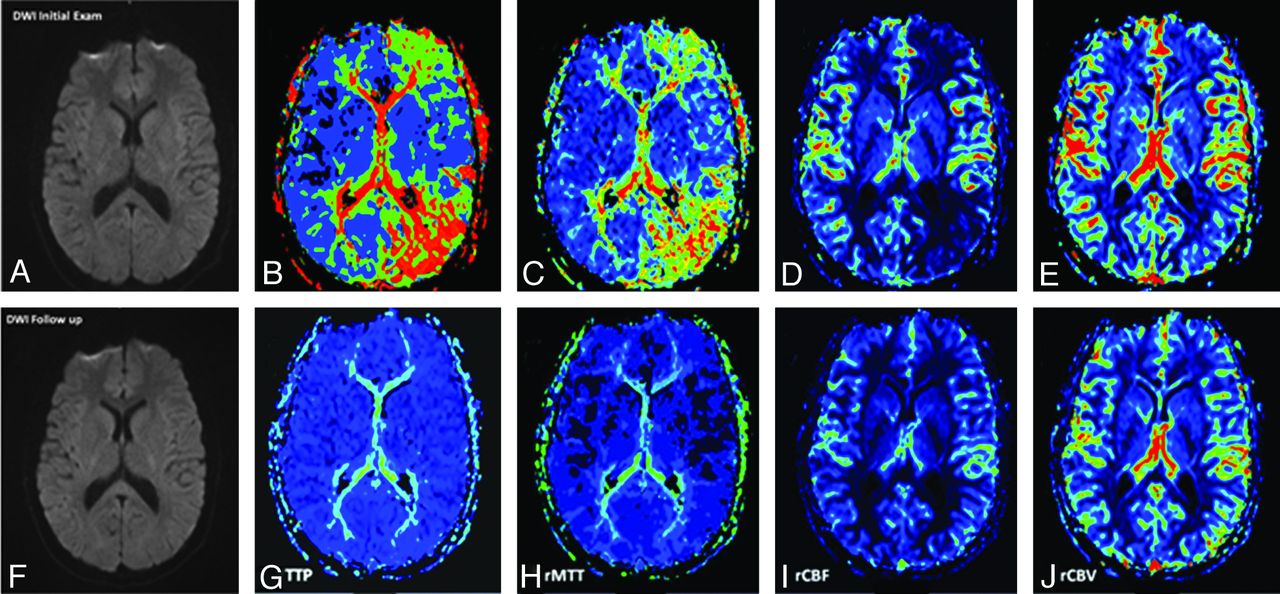

No other sequences showed any pathologic findings. In particular, there was no evidence of restricted diffusion (Fig 2).

A–F, A 17-year-old male patient with acute onset of aphasia and right-sided paresthesias: DWI findings were negative for ischemic brain infarction initially (A) and during follow-up (F). B–E, PWI demonstrates hypoperfusion in the posterior cerebral and, to a lesser degree, in the middle cerebral vascular territories on the left side—most pronounced in TTP (grade 3) and rMTT (grade 2) maps. rCBF maps demonstrated hypoperfusion grade 2; rCBV maps demonstrated hypoperfusion grade 1. G–J, Follow-up PWI after 24 hours shows complete resolution of hypoperfusion.

Clinical follow-up was available in all cases. In all patients, symptoms fully resolved, spontaneously (n = 5) or after treatment with IV acetylsalicylic acid or acetaminophen (n = 14). Systemic thrombolysis (alteplase) was performed in 1 patient with suspected stroke at the beginning of the study period (the first patient with migraine in this study). In 14/20 patients, follow-up examinations in a time interval of 20–30 hours (mean, 22 hours) were available. All follow-ups demonstrated complete resolution of hypoperfusion at visual assessment (Figs 2–⇓4). Repeat standard sequences demonstrated no change to the initial examination.